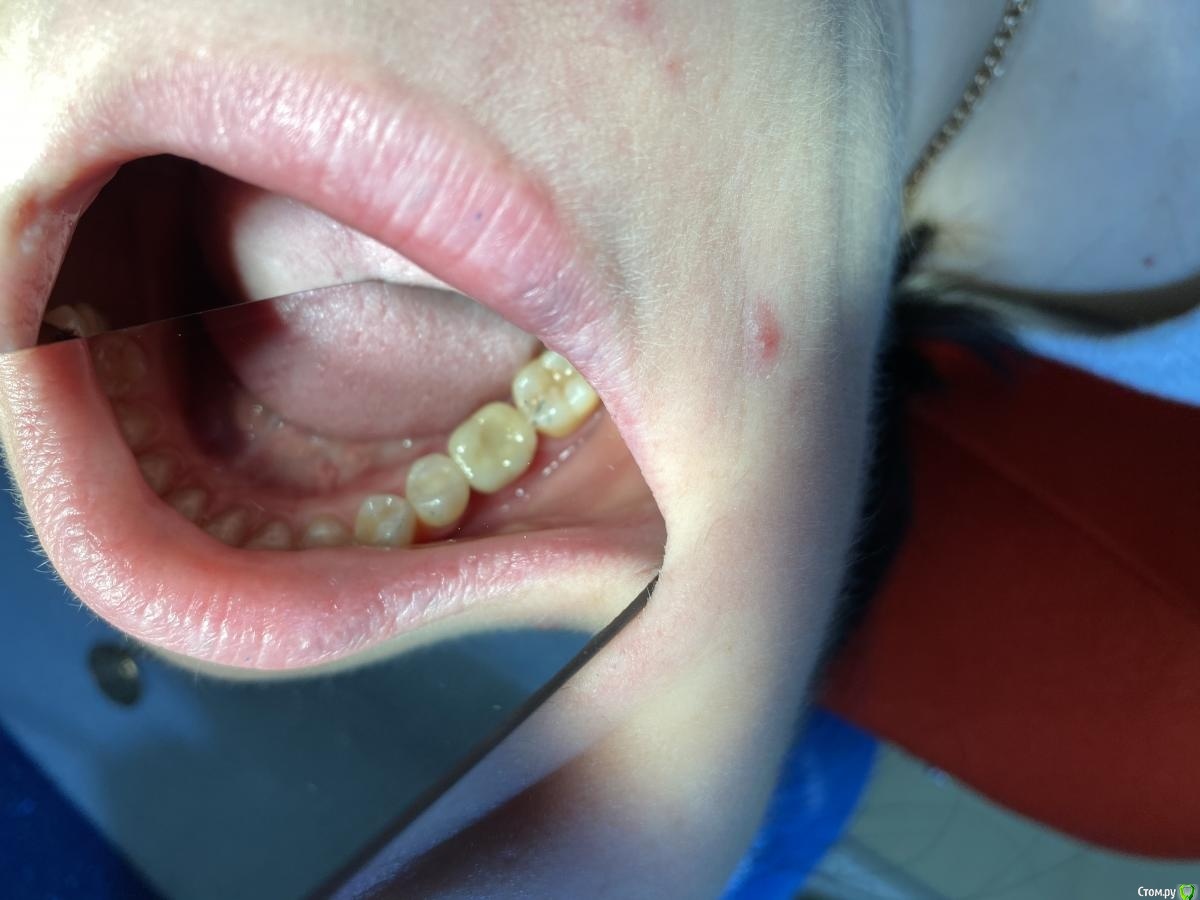

Женька Опубликовано 6 августа, 2020 Автор Поделиться Опубликовано 6 августа, 2020 (изменено) Язычный гребень выше вестибулярногоВроде тут хорошо видно, что как раз наоборот. Вестибулярный край десны выше, а язычно "яма".@Irouil, возвращаясь к 39 сообщению, немного не понял куда резать Может есть возможность схему какую-то показать или пример разрезов или вообще видеозапись. Изменено 6 августа, 2020 пользователем Женька Ссылка на комментарий

Женька Опубликовано 14 сентября, 2020 Автор Поделиться Опубликовано 14 сентября, 2020 Ну как-то вот так... Ссылка на комментарий

Irouil Опубликовано 14 сентября, 2020 Поделиться Опубликовано 14 сентября, 2020 (изменено) Не идеально, конечно, но я бы отправил уже на протезирование так на Вашем месте, прикрепленка есть, кортикалка по шейку Если включать перфекциониста, то можно пончо сделать, но нужно отслоиться через прикрепление эпителиальное, нужно и увеличение, и тунельный острый инструмент или микро хирургическое лезвие, и навык. Испортить тут можно гораздо больше, чем улучшить Основание абатмента пониже и пошире просто взять и пациента натаскать на гигиену, все ок будет Изменено 14 сентября, 2020 пользователем Irouil 1 Ссылка на комментарий

Женька Опубликовано 14 сентября, 2020 Автор Поделиться Опубликовано 14 сентября, 2020 Не идеально, конечно, но я бы отправил уже на протезирование так на Вашем месте, прикрепленка есть, кортикалка по шейку Если включать перфекциониста, то можно пончо сделать, но нужно отслоиться через прикрепление эпителиальное, нужно и увеличение, и тунельный острый инструмент или микро хирургическое лезвие, и навык. Испортить тут можно гораздо больше, чем улучшить Основание абатмента пониже и пошире просто взять и пациента натаскать на гигиену, все ок будетЯ придерживаюсь этого же мнения...Я скорее испорчу то, что получилось. Эти фото с формирователем 4.5, 3 месяца ходили с 4.0На этапе прикручивания 4.5, пациентка отметила легкое жжение... на фдм метрогил был...вот думаю, то ли это на метрогил такая реакция, то ли я что-то задавил? Планировали на тибейзе geo делать... там варианта пошире насколько я знаю нет. 4.5 и размеры по вертикали cut и длинные З.Ы. Вчера у Ильгама Ирековича на курсе впервые познакомился с галилеями от экзама... всего 2.8, быстро привыкли глаза (учитывая, что они не индивидуально под меня были)... это просто какой-то другой мир. Ссылка на комментарий